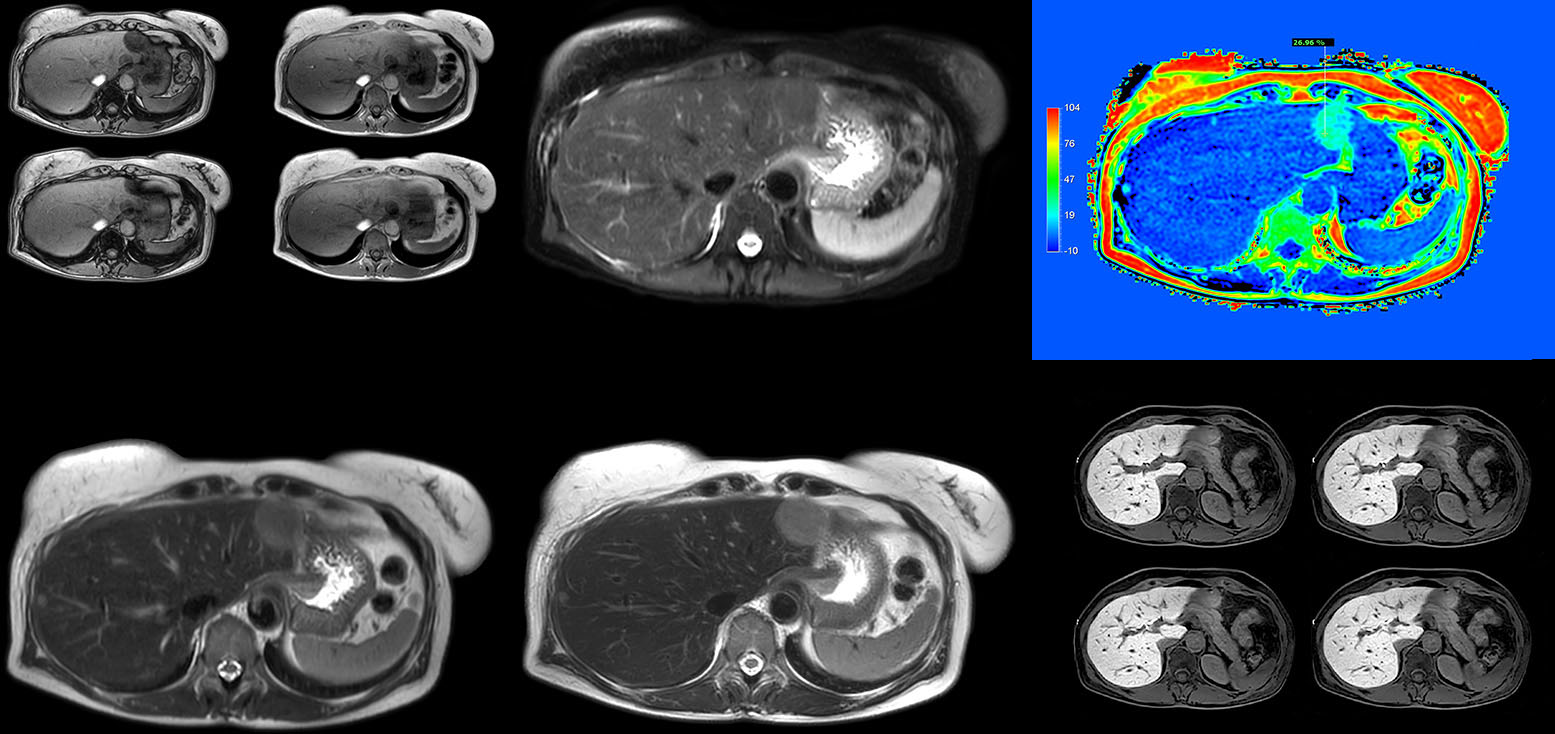

Dr. Kukuk scans an increasing number of liver patients in an arms-up position using the integrated Posterior coil and a special positioning device. “By placing the patient’s arms up, the field of view in the right-left direction can be smaller so that a right-left preparation direction can be used to cut down the scan time,” he explains. “We can use high dS SENSE factors for TSE imaging, so we can shorten the echo train length. This results in a faster scan than arms-down T2 TSE and the images show high anatomical detail.”

“For DWI, the high dS SENSE factor allows using a shorter TE so we get higher signal and fewer susceptibility artifacts, which means less distortion of diffusion weighted images. Of course, with higher dS SENSE factors and the shortening of the TSE factor in T2-weighted imaging, we can drastically cut down the complete examination time. So, with arms-up we get faster images, less distortion in DWI and less blurring on T2-weighted images. Almost all patients tolerate the arms-up scanning well.”

“We get fast images, less distortion in DWI and less blurring on T2-weighted images.”